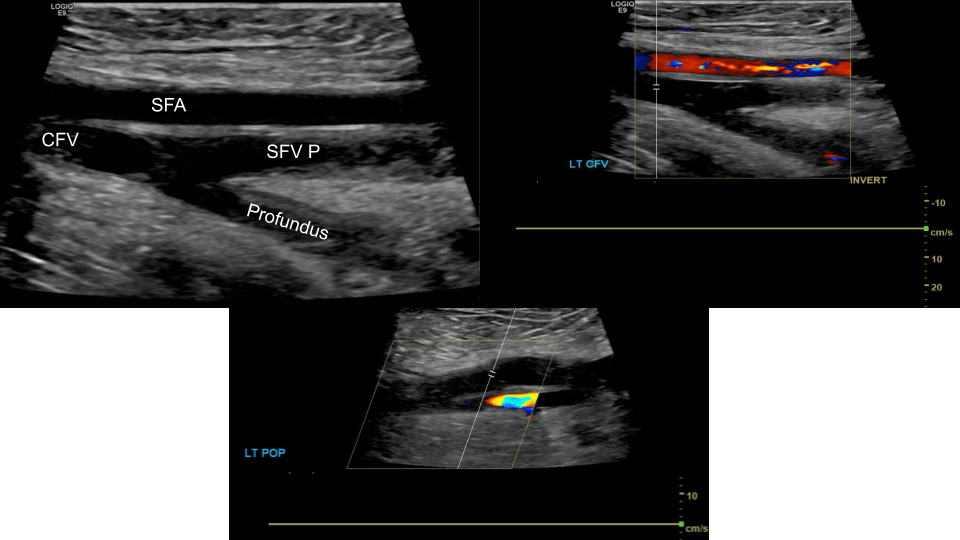

The CFV bifurcates into femoral vein (formerly superficial femoral vein, SFV) and the profundus or deep femoral vein. the SFV courses inferiorly to become the popliteal vein (POP), from the popliteal vein the trio of anterior, posterior tibial and peroneal (fibular) veins arises from the tibio-peroneal trunk.

These form the major veins we evaluate during a lower extremity duplex.

Common Femoral Vein: Dual image with compression, grayscale, color doppler, color doppler and pulsed wave doppler

Femoral Vein: Dual image with compression, greyscale, color doppler, color doppler and pulsed wave doppler (scan proximal to distal)

Popliteal Vein: Dual image with compression, greyscale, color doppler, color doppler and pulsed wave doppler